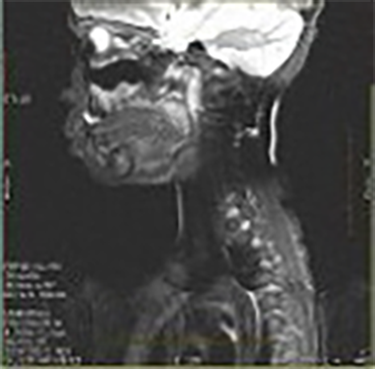

| Bulk Susceptibility (C-spine Fat Sat Uniformity) Poor chemical fat sat uniformity | ![]() | Poor B0 uniformity |